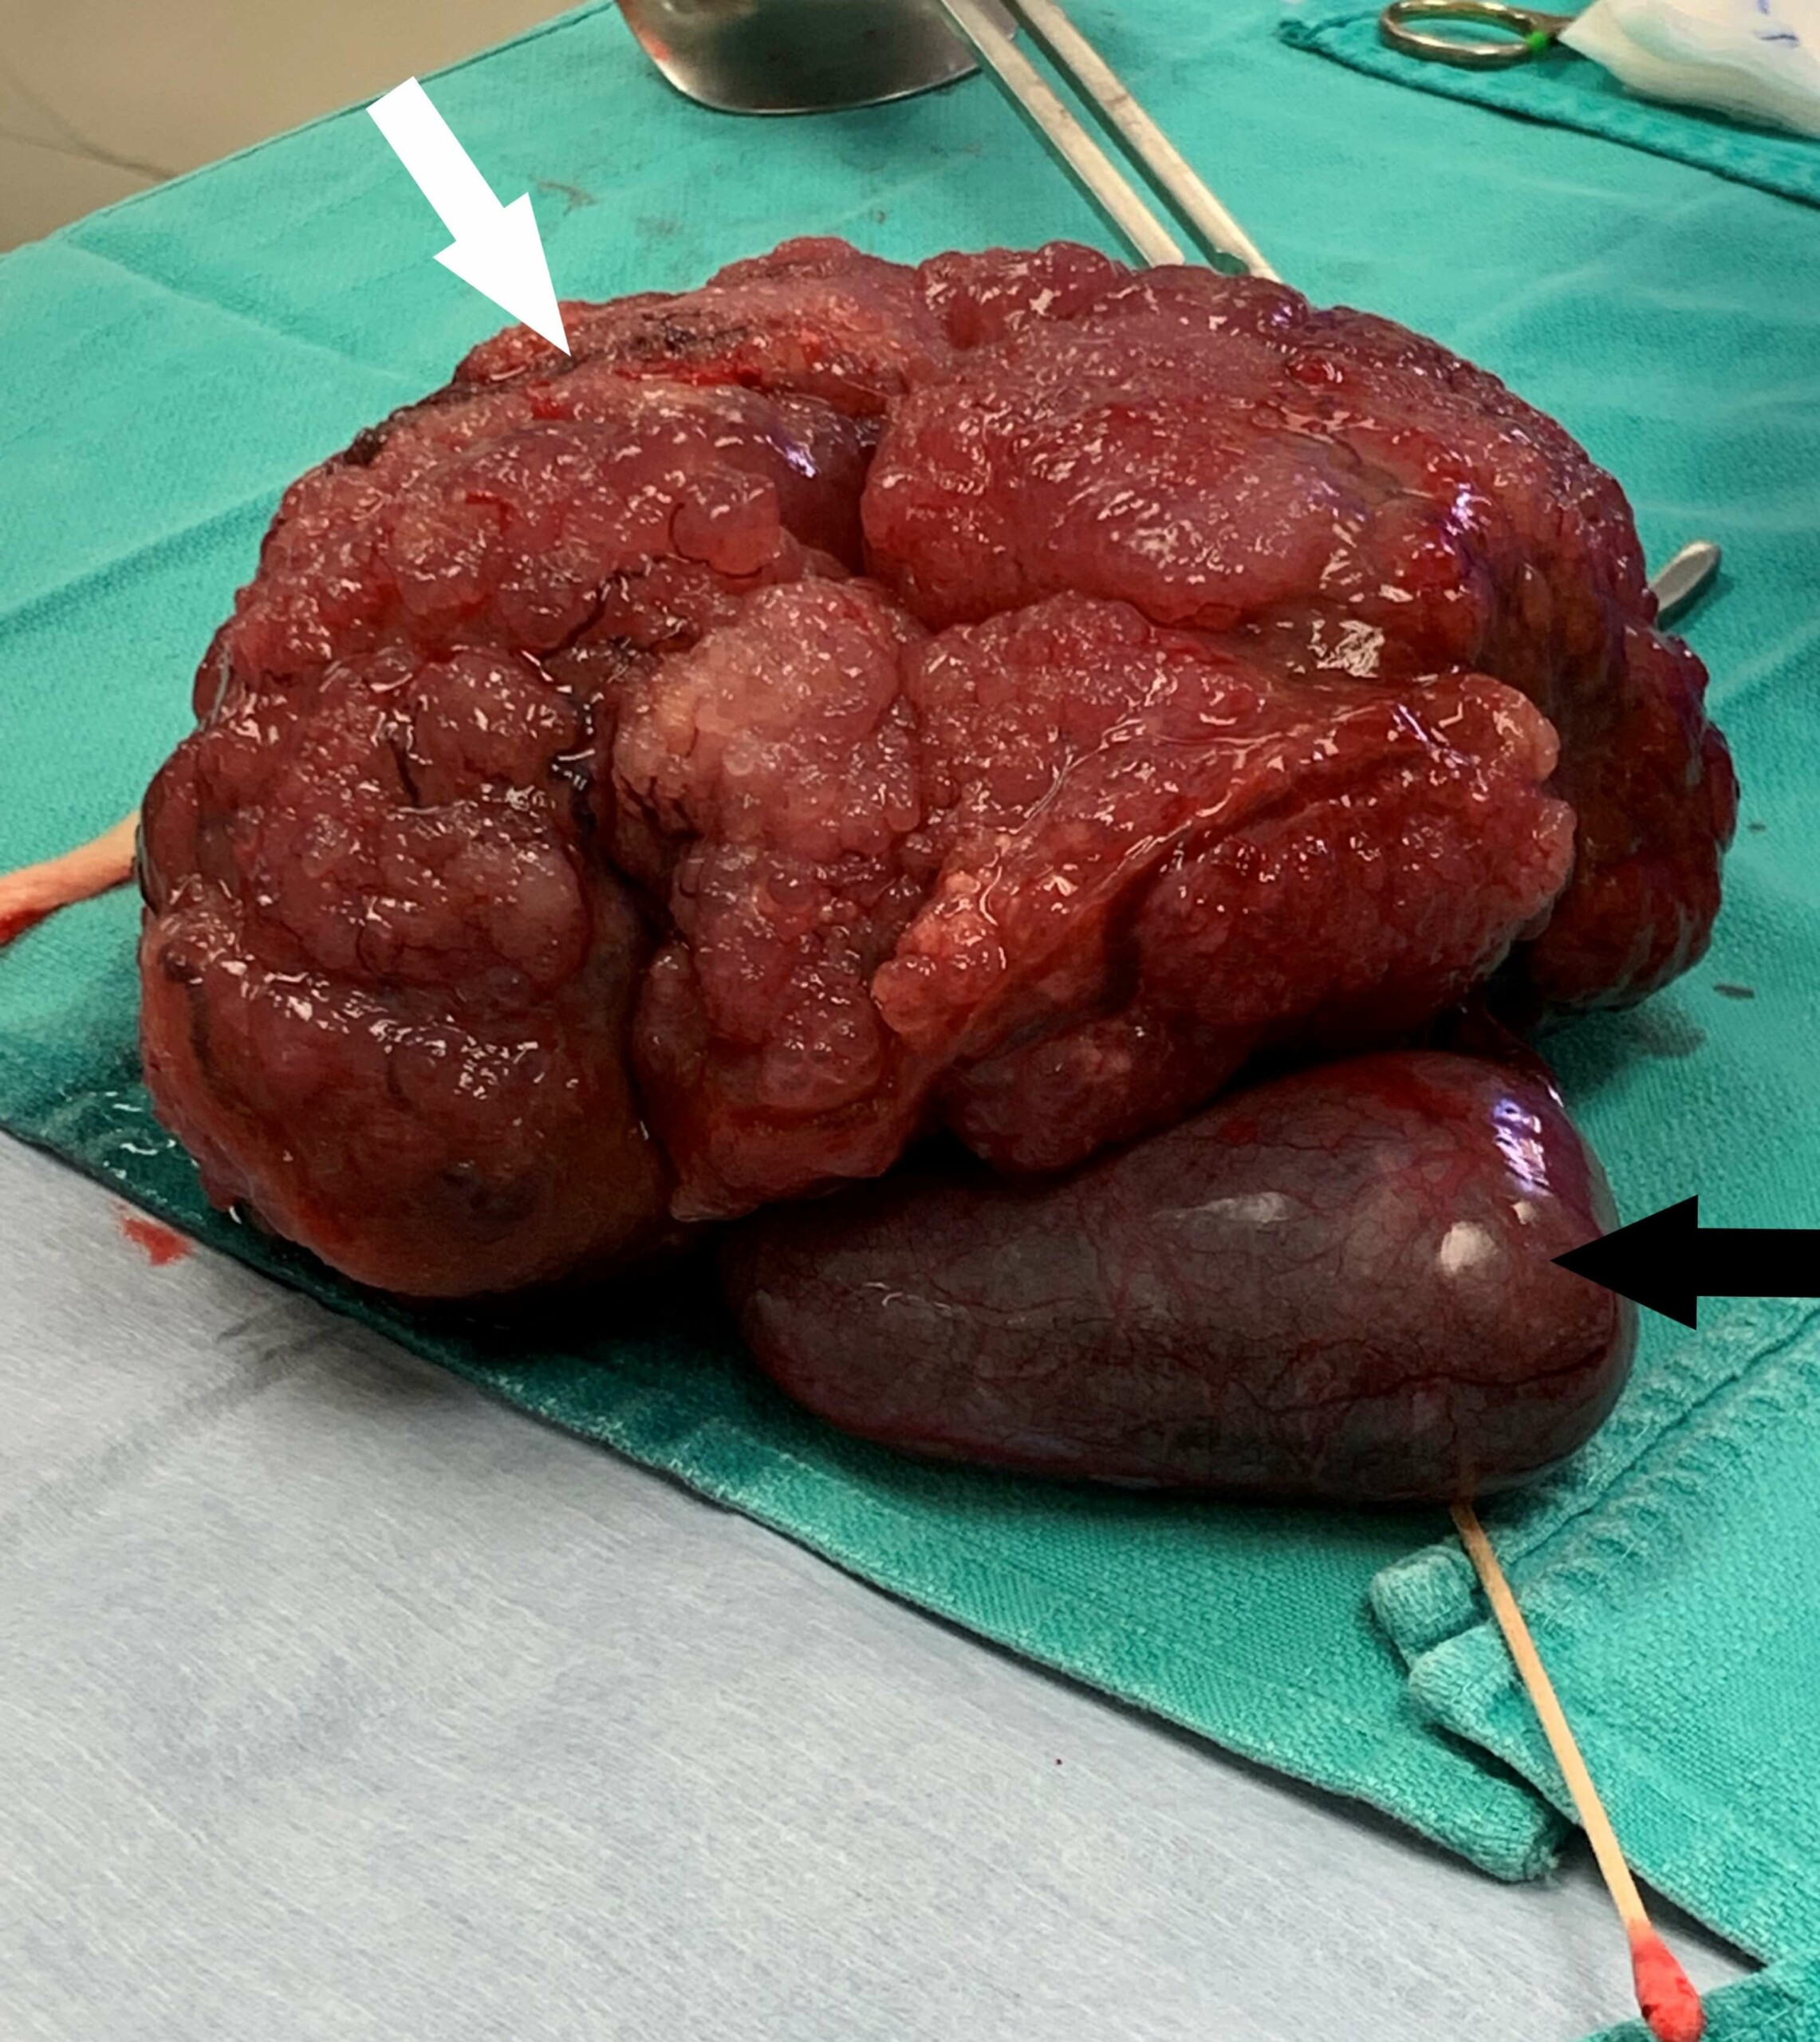

After performing the contrast CT scan, abdominal exploration was elected by the owners. Our surgical team performed a complete central hepatectomy removing the right medial liver lobe, quadrate liver lobe, and gall bladder all at once. A postoperative picture of the mass is seen below. Reilly recovered well from his procedure and was discharged the next day. The mass was sent for histopathology and the final results were definitive for cholangiocarcinoma, an extremely uncommon diagnosis for liver tumor. For the past 20 months, our Oncology team has closely monitored Reilly and have not seen any evidence of tumor recurrence to date.